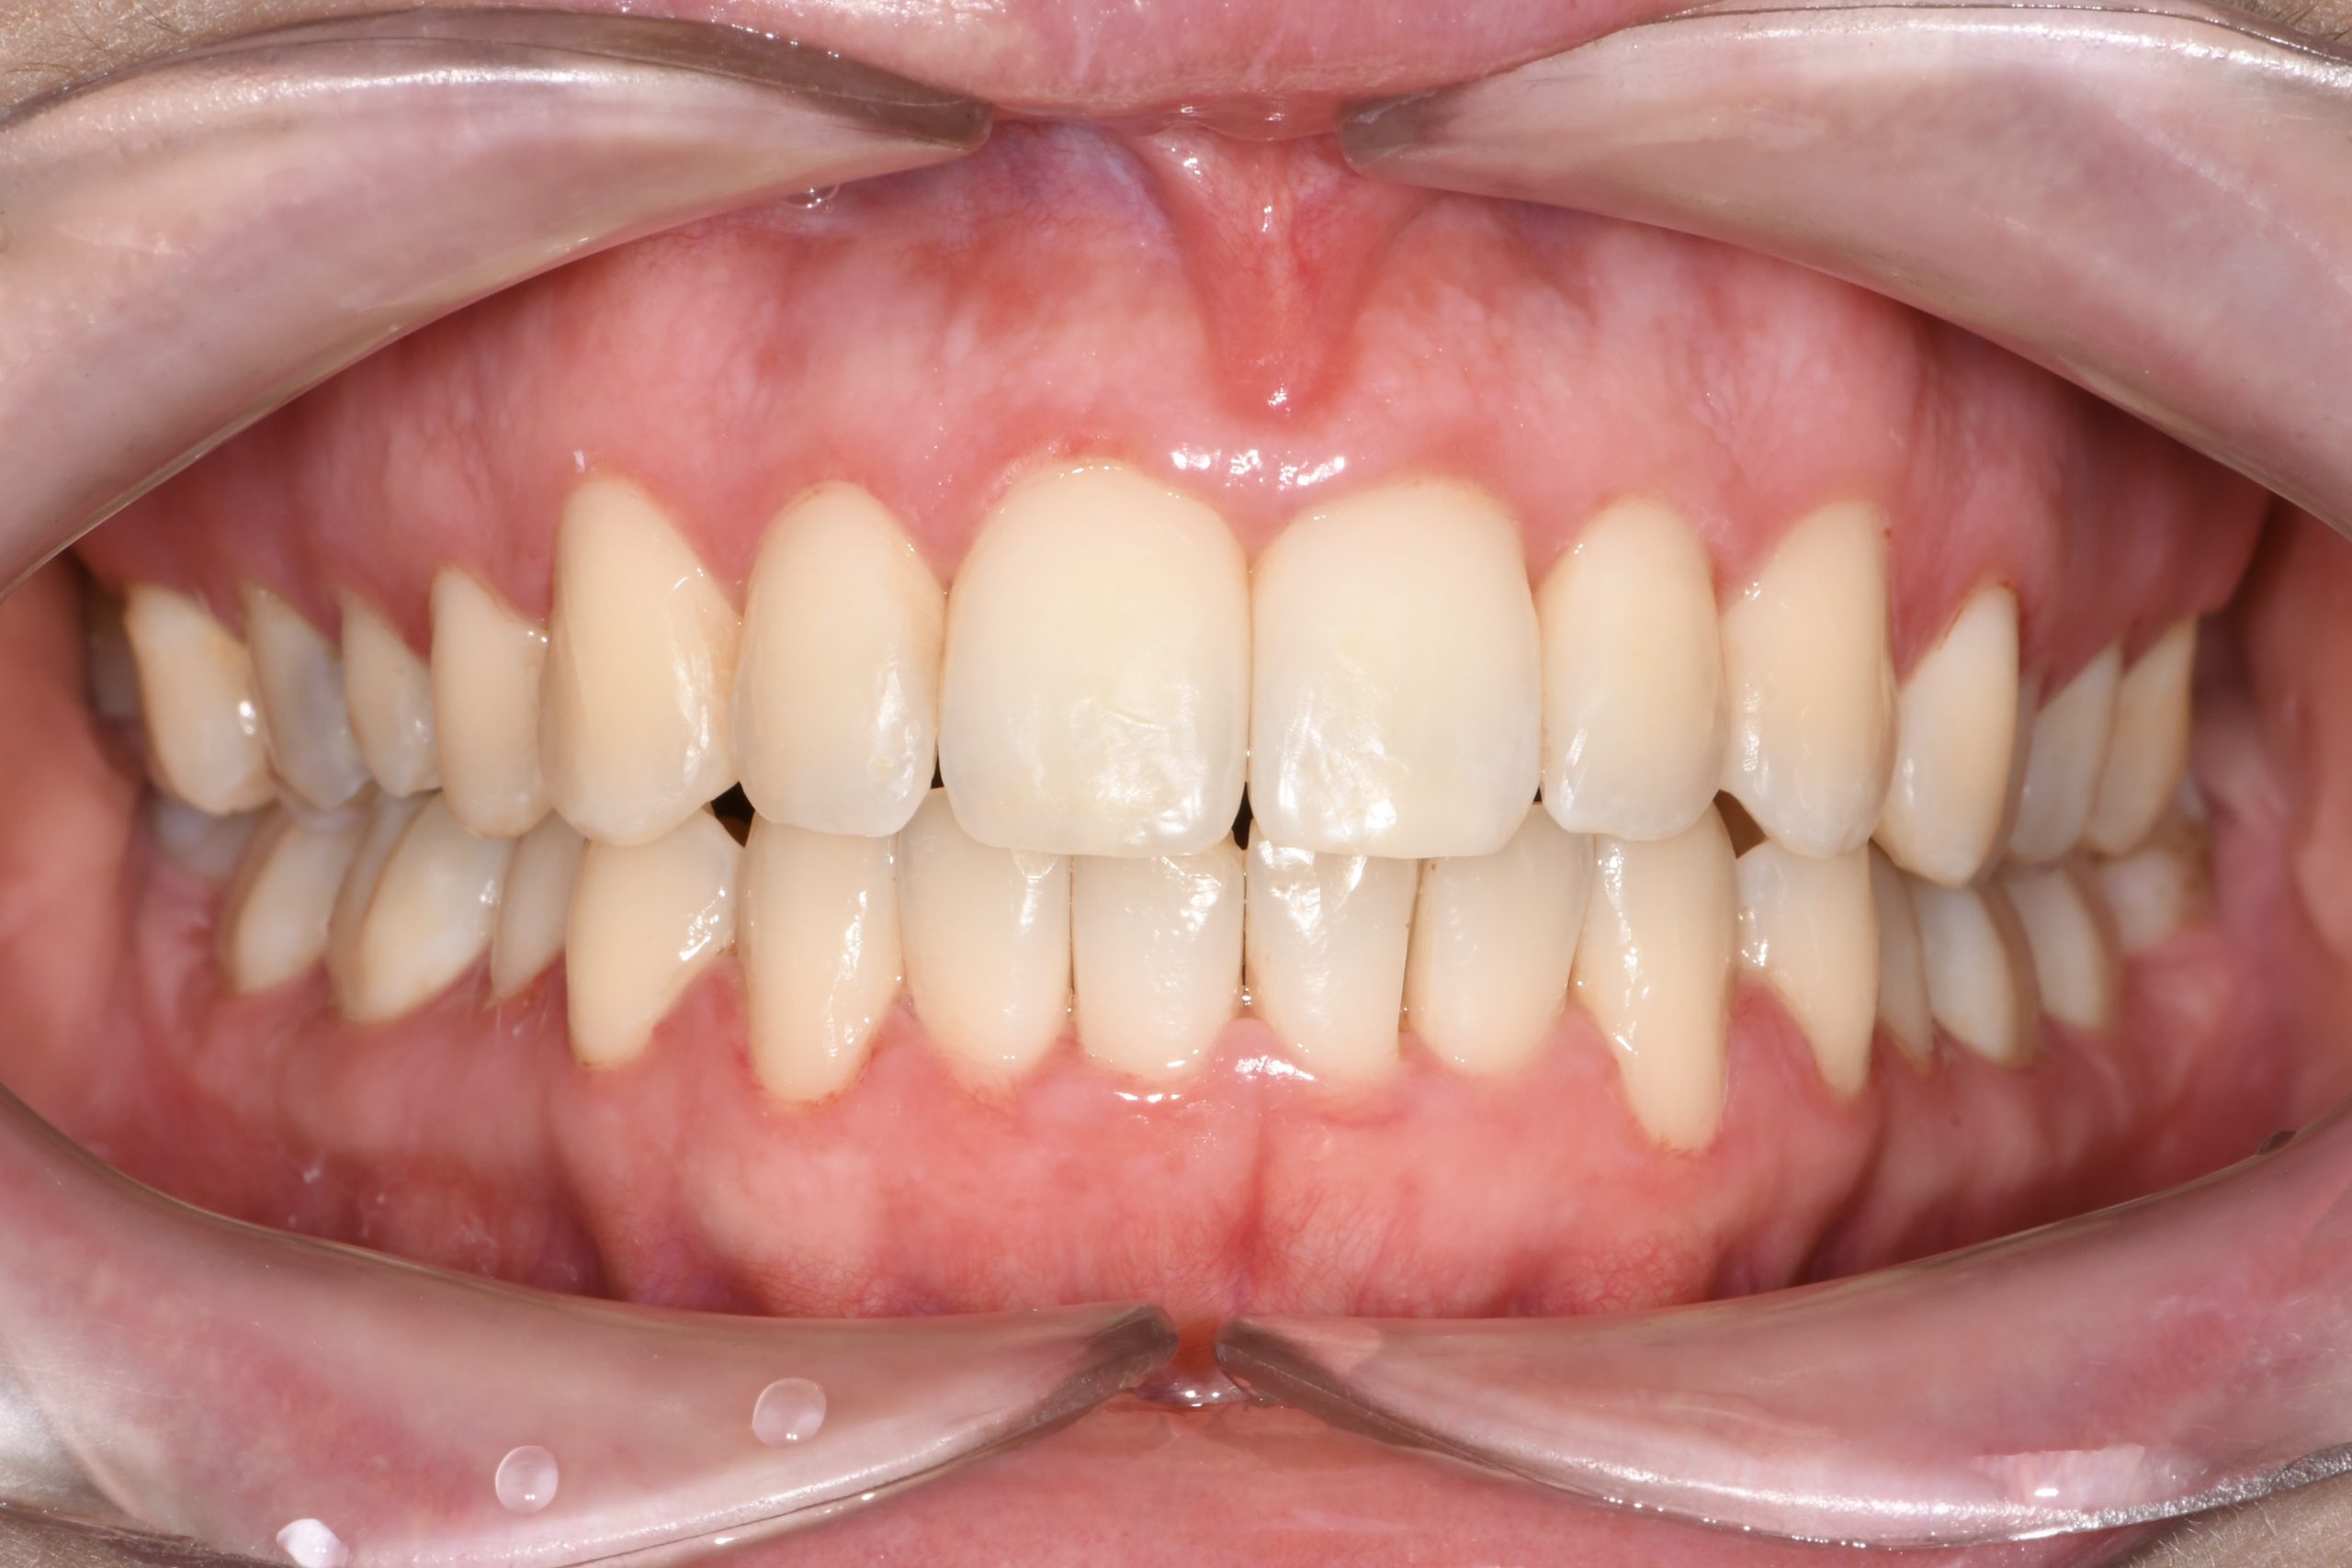

Az elmúlt évekből rengeteg szakmai referenciát tudnánk bemutatni, amelyek különböző fogszabályozási problémákat oldottak meg. Válogatva a több száz esetből, ezen az oldalon olyan képeket, információkat igyekeztünk bemutatni, amelyeknek a segítségével a jövőbeni pácienseinknek azt tudjuk üzenni: A Te fogsorod is lehet gyönyörű!

(Képeket a Pácienseink külön írásos beleegyezésével mutatjuk be!)